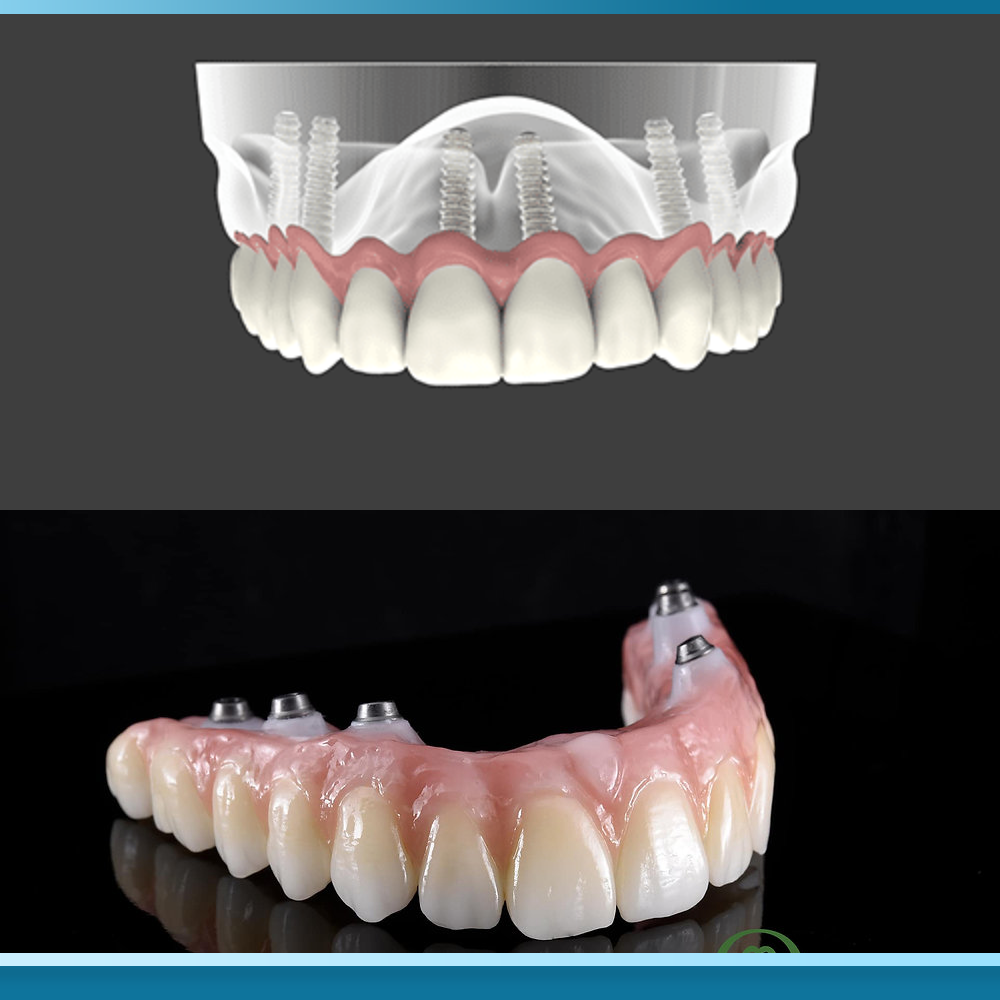

Kỹ thuật All on 6 là giải pháp phục hình răng toàn hàm cố định hiện đại, sử dụng sáu trụ Implant bằng Titanium cấy ghép vào xương hàm để nâng đỡ một cầu răng sứ gồm 12 đến 14 răng. Các trụ này đóng vai trò như những chân răng nhân tạo, sau quá trình tích hợp xương (Osseointegration) – hiện tượng các tế bào xương bám chặt vào bề mặt Implant – chúng tạo thành một khối thống nhất và vững chắc.

Ngược lại, hàm phủ trên Implant (Overdenture) là một giải pháp phục hình bán cố định, kết hợp giữa kỹ thuật Implant và hàm giả tháo lắp truyền thống. Thay vì gắn cố định bằng vít hoặc xi măng, Overdenture sử dụng từ hai đến bốn trụ Implant làm điểm neo giữ, kết nối với hàm giả thông qua các hệ thống khóa cài như bi (ball), thanh bar hoặc locator (một loại khóa cài chính xác).